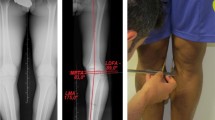

Coronal alignment of the lower limbs was determined by measuring inter-condylar (ICD) and inter-malleolar (IMD) distances with a calliper [8, 10]. Subjects stood in a relaxed, upright position with both feet pointing straight forward, hips and knees maximally extended and touching the medial femoral condyles or medial malleoli. Positive ICD-IMD values indicate increased intercondylar distance (varus alignment), while negative ICD-IMD values indicate increased intermalleolar distance (valgus alignment). All measurements were performed alternately by two trained examiners and repeated three times for each participant. The technical details of the measurement are described in Krajnc et al. [23].

The interaction of the factors age and sport was not significant (p = 0.892; ηp2 = 0.009; 1 − β = 0.110), so there were no statistically significant differences between the two sport groups at any age. There was a highly significant effect of the age factor (p < 0.001; ηp2 = 0.281; 1 − β = 0.999) and a non-significant effect of the sport factor (p = 0.437; ηp2 = 0.005; 1 − β = 0.121). The results of the post hoc analysis showed a statistically significant increase (p < 0.05) in ICD-IMD values between 12 and 16 years (12 years; football 0 mm ± 162 mm; ice hockey − 64 mm ± 272 mm, 13 years; football 123 mm ± 203 mm; ice hockey 35 mm ± 167 mm, 14 years; football 233 mm ± 225 mm; ice hockey 268 mm ± 306 mm, 15 years; football 271 mm ± 233 mm; ice hockey 260 mm ± 109 mm, 16 years; football 340 mm ± 199 mm; ice hockey 310 mm ± 131 mm) in both sport groups (Fig. 1). Both sports groups showed a significant increase in ICD-IMD values compared to the general population; football players at age 13 (general population: − 75 mm ± 238 mm, football players: 123 mm ± 203 mm, p = 0.001) and ice hockey players at age 14 (general population 52 mm ± 291 mm; ice hockey players 268 mm ± 306 mm, p = 0.003).

The following limitations of our methodology need to be considered. First, the sample size was small and we did not include a control group of non-athletic peers. However, we used previously published data from non-athletes in a comparable age range [3, 17], which clearly showed that both sport groups had higher ICD-IMD values at a given age. Secondly, standing height and leg length were not taken into account when comparing ICD-IMD values between age groups. Since we studied young players with active longitudinal bone growth, the observed increase in the absolute value of ICD-IMD may not be a pure representation of changes in varus/valgus position of the knee. The increase in ICD-IMD value could be a function of the increase in bone length and not the change in hip-knee-ankle angle. However, Cahuzac et al. [9] found no correlation between height and ICD-IMD distance, so absolute ICD-IMD values were used in most alignment studies [3, 7, 8, 15, 17, 21]. Thirdly, the measurement of intercondylar and intermalleolar distance cannot distinguish between possible asymmetries in the alignment of the left and right knee. Furthermore, there is a possibility of subjective bias when measuring ICD-IMD with a calliper. Therefore, in the presented study, great attention was paid to the standardisation of the measurement protocol and the measurements were repeated alternately by the two trained investigators. Krajnc and Drobnič [19, 23] had shown that the clinical measurement ICD-IMD values correlates well with the results of radiographs, therefore the method can be considered valid for population studies.